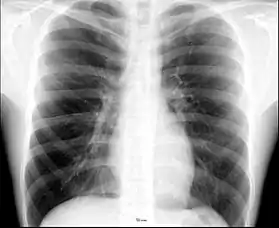

الصدر، عرض أمامي.